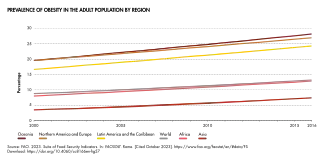

Obesity is a leading preventable cause of death worldwide, with increasing rates in adults and children.[18] In 2022, over 1 billion people lived with obesity worldwide (879 million adults and 159 million children), representing more than a double of adult cases (and four times higher than cases among children) registered in 1990.[7][19] Obesity is more common in women than in men.[1] Obesity is stigmatized in most of the world. Conversely, some cultures, past and present, have a favorable view of obesity, seeing it as a symbol of wealth and fertility.[2][20] The World Health Organization, the US, Canada, Japan, Portugal, Germany, the European Parliament and medical societies (such as the American Medical Association) classify obesity as a disease. Others, such as the UK, do not.[21][22][23][24]

In 1997, the WHO formally recognized obesity as a global epidemic.[115] As of 2008, the WHO estimates that at least 500 million adults (greater than 10%) are obese, with higher rates among women than men.[218] The global prevalence of obesity more than doubled between 1980 and 2014. In 2014, more than 600 million adults were obese, equal to about 13 percent of the world's adult population,[219] with that figure growing to 16% by 2022, according to the World Health Organization.[220] The percentage of adults affected in the United States as of 2015–2016 is about 39.6% overall (37.9% of males and 41.1% of females).[221] In 2000, the World Health Organization (WHO) stated that overweight and obesity were replacing more traditional public health concerns such as undernutrition and infectious diseases as one of the most significant cause of poor health.[222]

The rate of obesity also increases with age at least up to 50 or 60 years old[52]: 5 and severe obesity in the United States, Australia, and Canada is increasing faster than the overall rate of obesity.[30][223][224] The OECD has projected an increase in obesity rates until at least 2030, especially in the United States, Mexico and England with rates reaching 47%, 39% and 35%, respectively.[225]

Once considered a problem only of high-income countries, obesity rates are rising worldwide and affecting both the developed and developing world.[226] These increases have been felt most dramatically in urban settings.[218] In 2021, nearly half the global adult population - a billion men and 1.11 billion women aged 25 or older - were overweight or obese. It was predicted that if these trends continue about 57.4% of men and 60.3% of women would be overweight or obese by 2050.